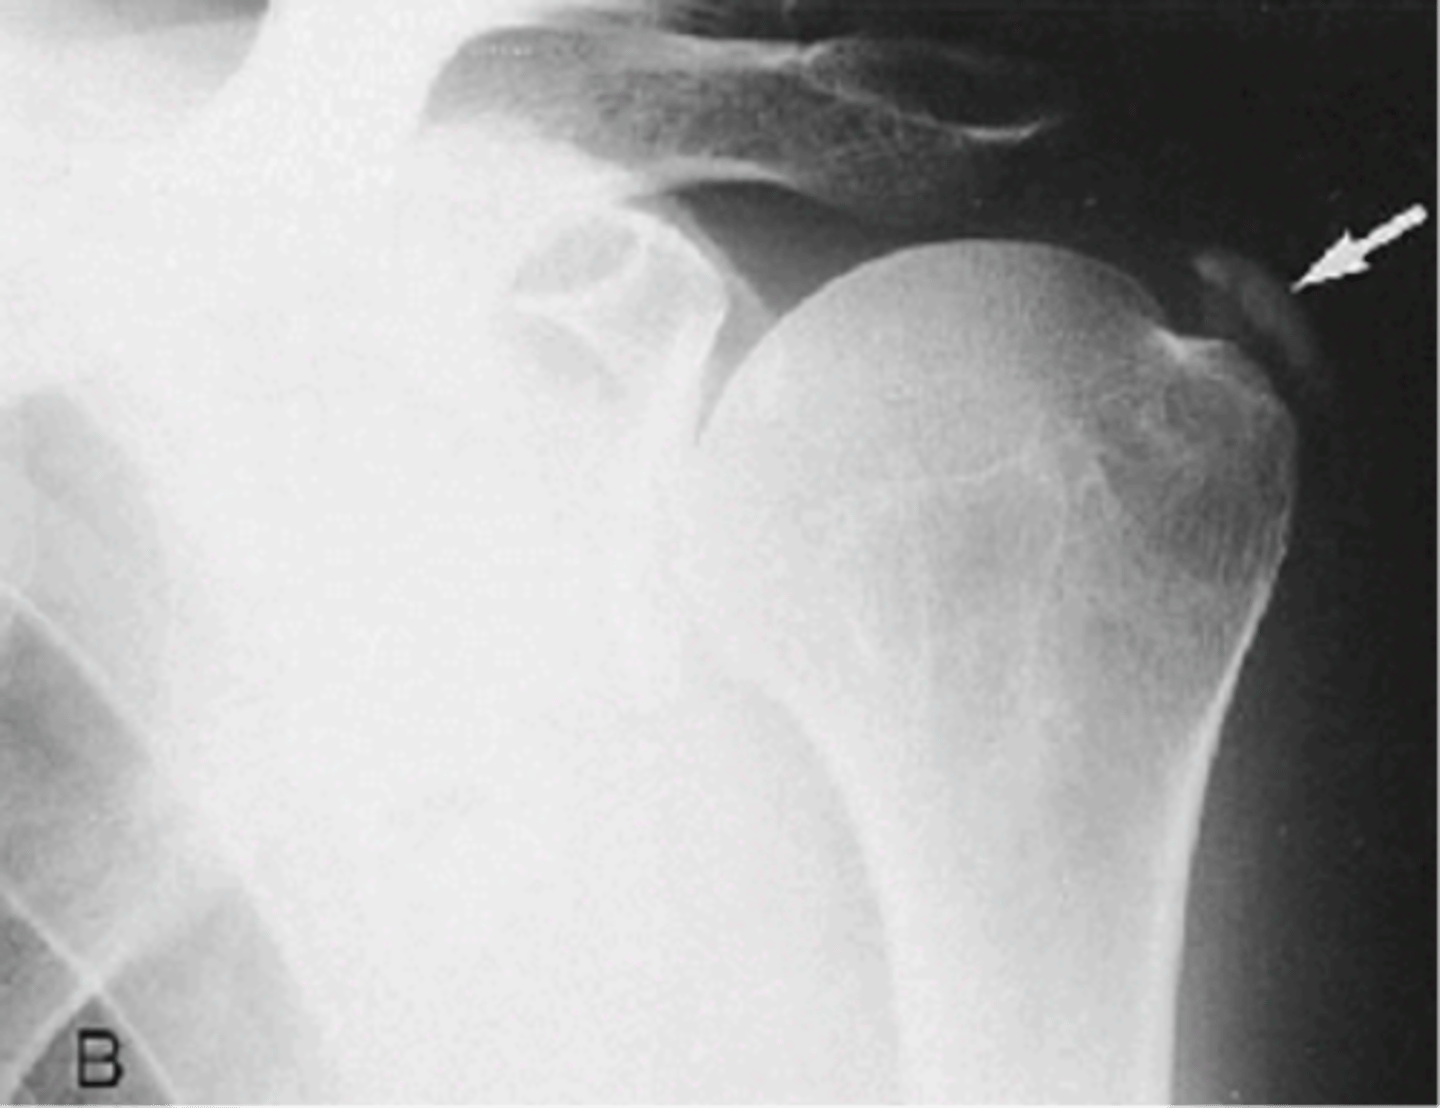

- Deposition of calcium hydroxyapatite within a tendon, bursa, or other periarticular soft tissue

- May cause tendinitis, bursitis, and joint pain

- 40-70 y.o.a

- M=F

- Pain, tenderness, localized swelling

- Decreased ROM

State the clinical features of hydroxyapatite deposition disease (HADD)

Calcific tendinitis

Another term for hydroxyapatite deposition disease (HADD)

Supraspinatus

Hydroxyapatite deposition disease (HADD) of the _____

Infraspinatus